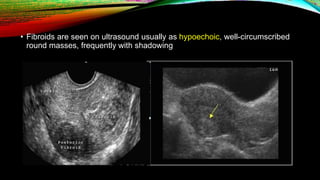

• Fibroids are seen on ultrasound usually as hypoechoic, well-circumscribed

round masses, frequently with shadowing

PELVIC ULTRASOUND • Pelvicultrasound is the first-line study used to evaluate for uterine fibroids. • Transvaginal ultrasound has high sensitivity (95 to 100 percent) for detecting myomas in uteri less than 10 gestational weeks' size. • Precise localization of fibroids is limited in larger uteri or when there are many tumors.

• Fibroids areseen on ultrasound usually as hypoechoic, well-circumscribed round masses, frequently with shadowing